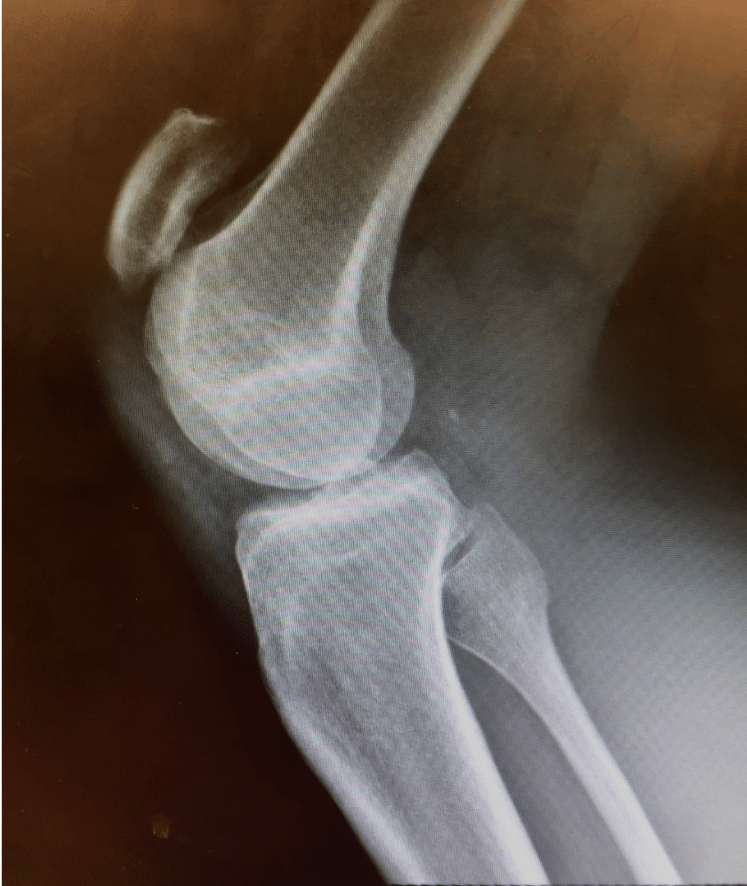

A Case of Traumatic Knee Pain Gepost op 26 november 2019 door netwerkvsseh Back to Basics: A Case of Traumatic Knee Pain @emdaily.cooperhealth.org Dit delen: Delen op X (Opent in een nieuw venster) X Share op Facebook (Opent in een nieuw venster) Facebook Delen op LinkedIn (Opent in een nieuw venster) LinkedIn E-mail een link naar een vriend (Opent in een nieuw venster) E-mail Afdrukken (Opent in een nieuw venster) Print Vind-ik-leuk Aan het laden... Gerelateerd